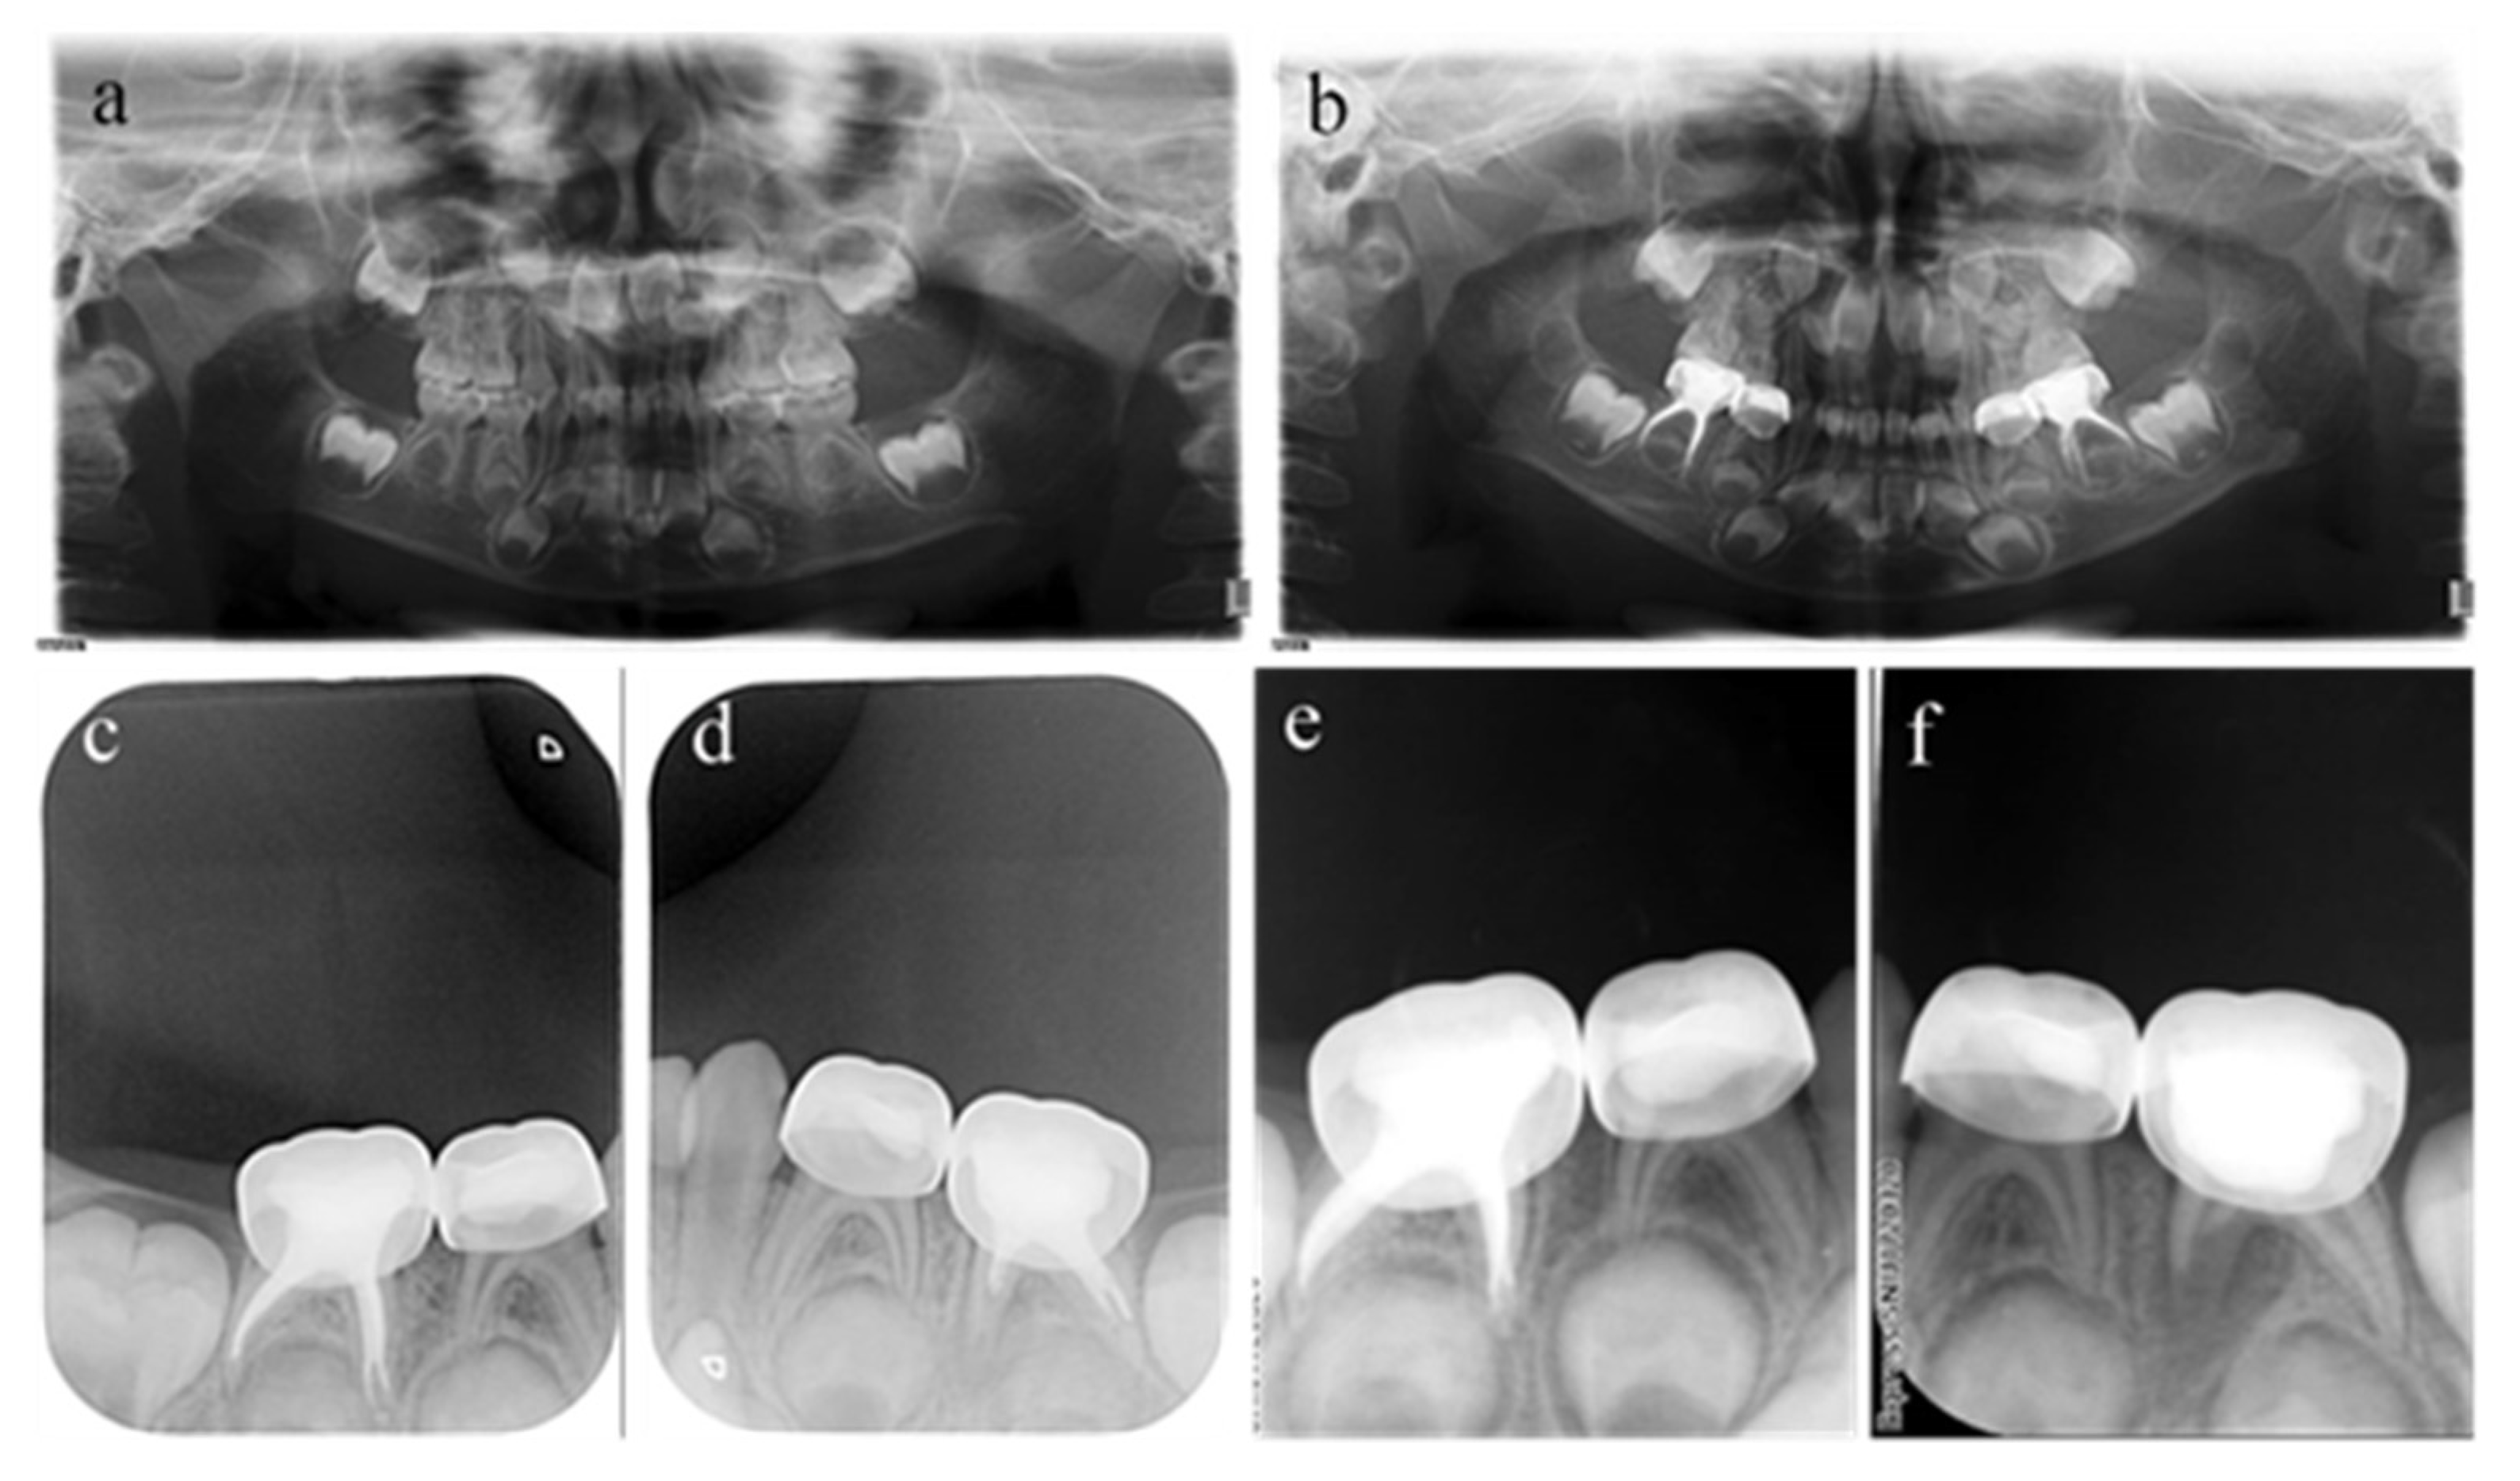

Figure 5.

#54 received pulpectomies under DGA with a 34-month follow-up period (65-month-old male child). (a) The preoperative radiograph revealed periapical radiolucency surrounding #54. (b) Radiograph taken one week postoperatively showing overfilling in the buccal root canals. (c) Twenty-six months after the operation, the root was completely absorbed, and the eruption direction of #14 was altered. Pulpectomies in #54 failed.